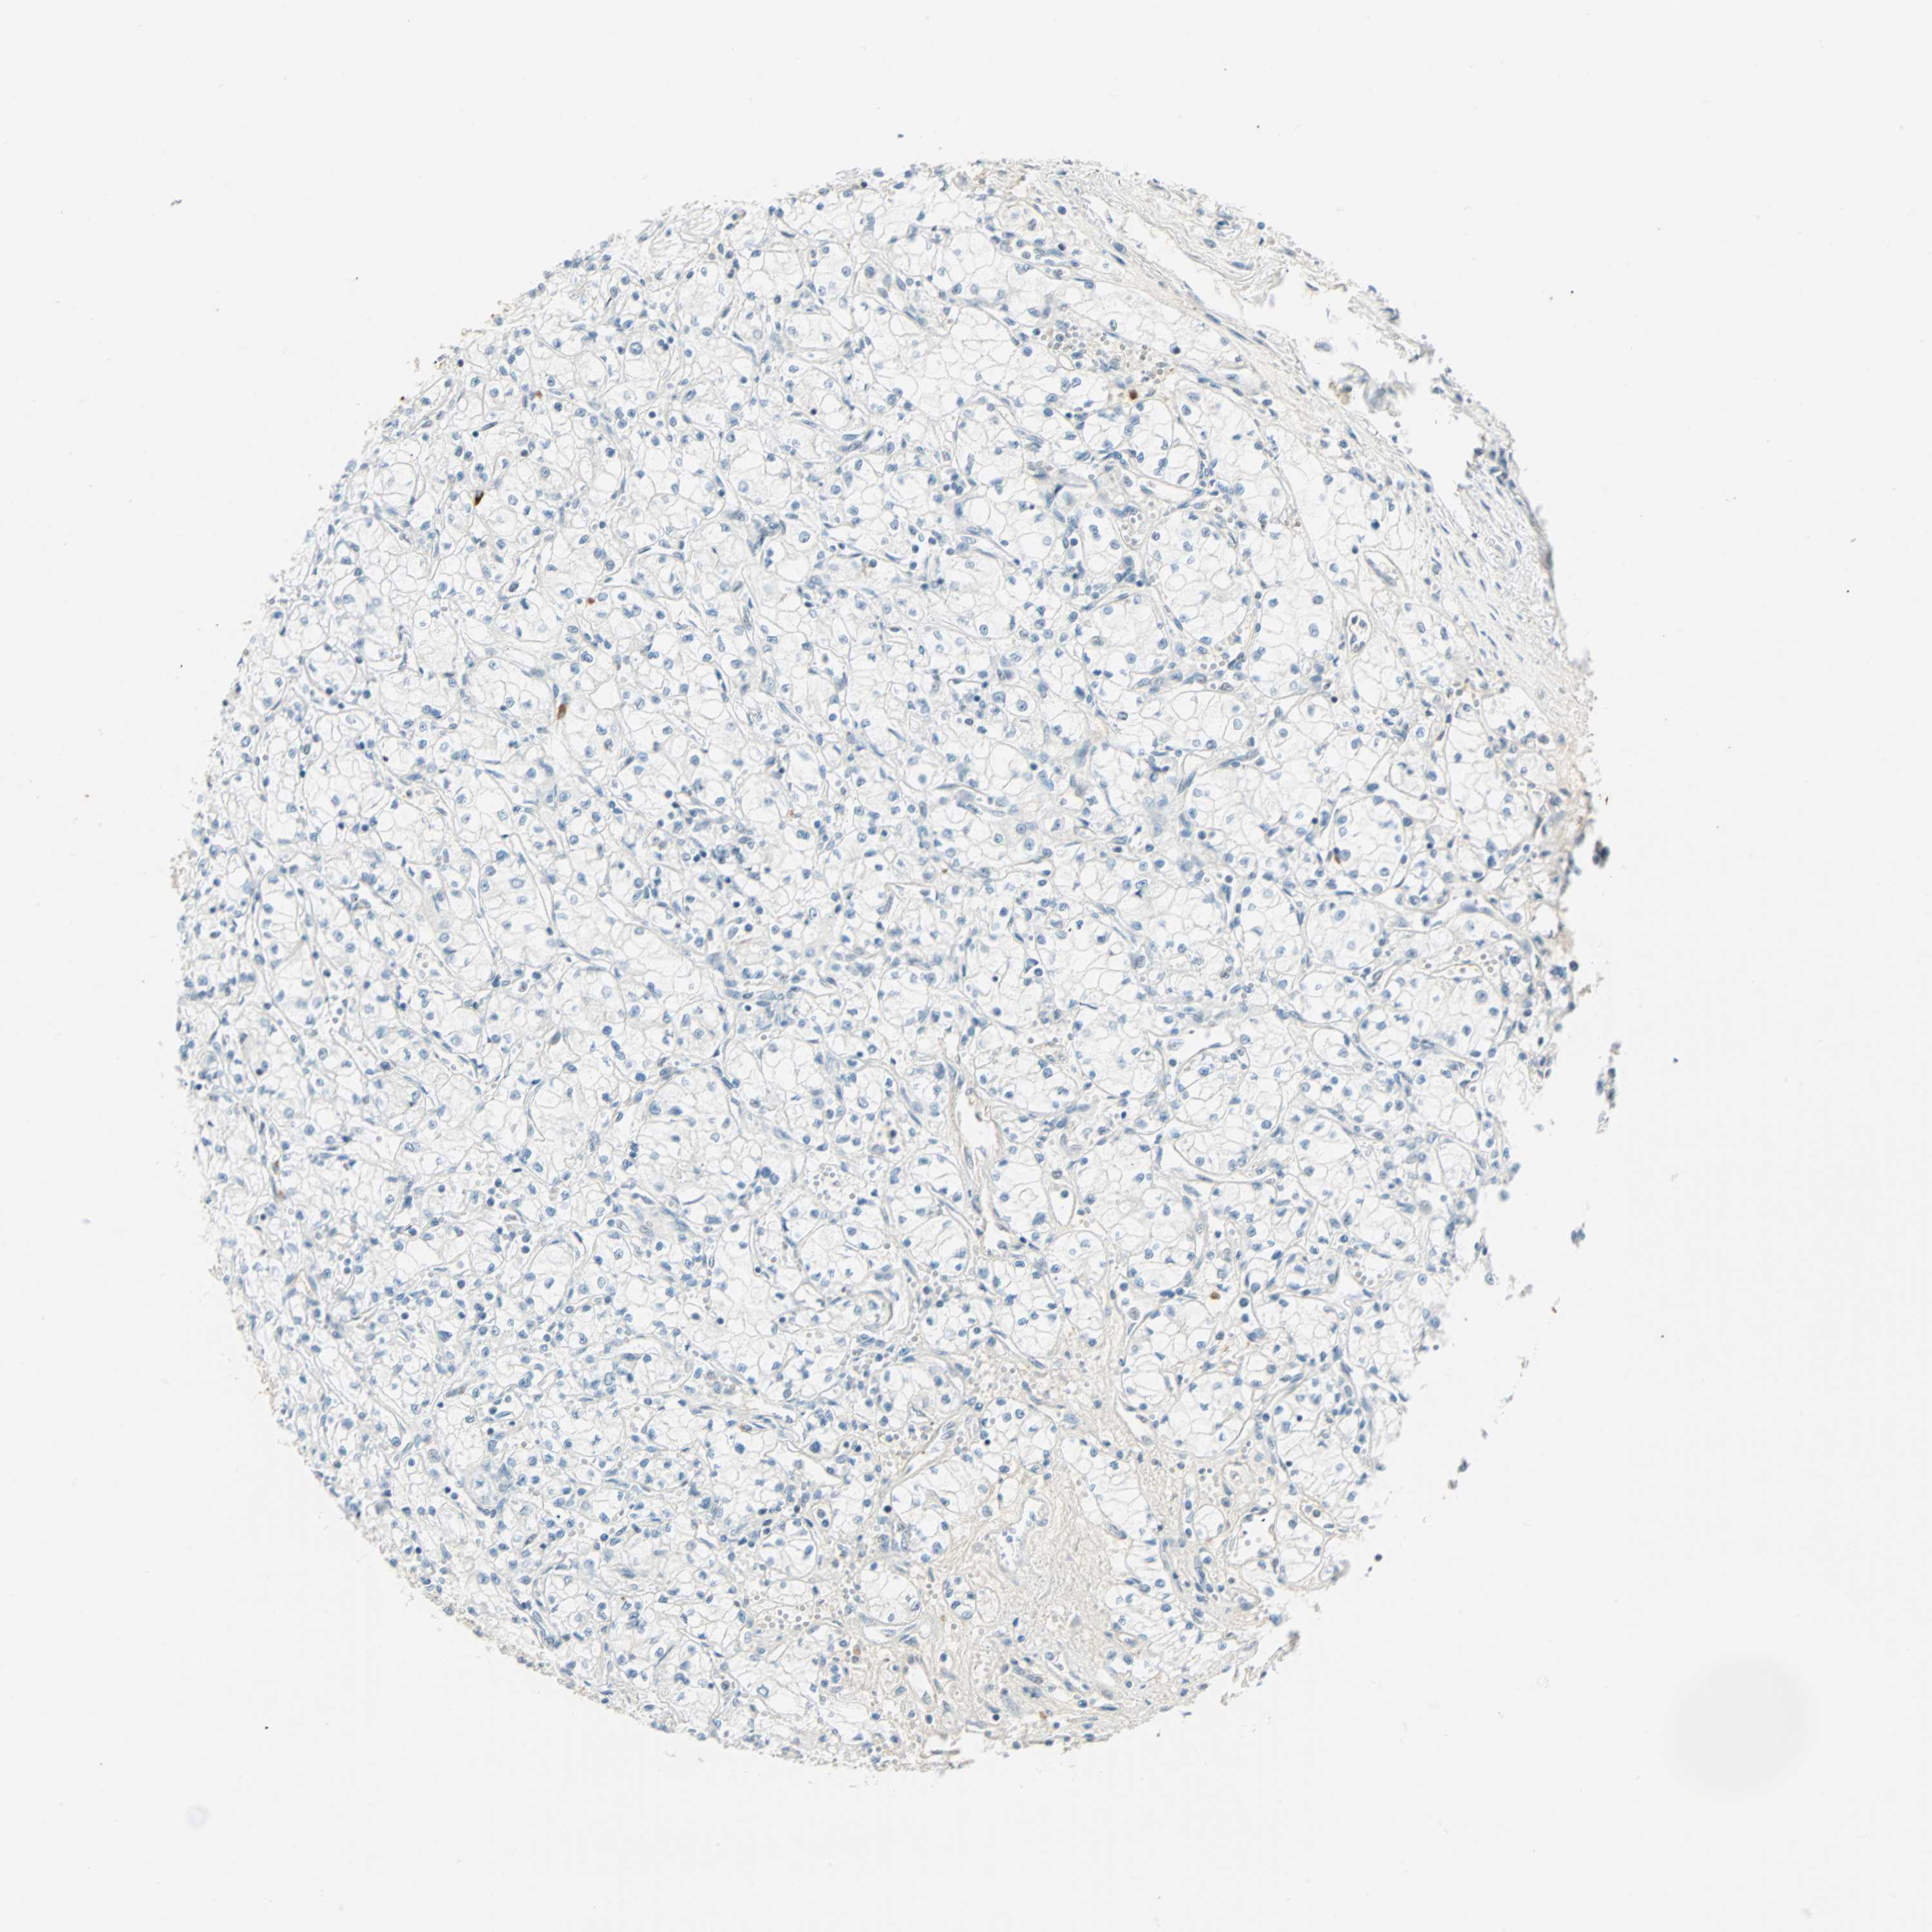

KIDNEY RENAL PAPILLARY CELL CARCINOMA (TCGA) - Interactive survival scatter ploti

The Survival Scatter plot shows the clinical status (i.e. dead or alive) for all individuals in the patient cohort, based on the same data that underlies the corresponding Kaplan-Meier plots. Patients that are alive at last time for follow-up are shown in blue and patients who have died during the study are shown in red.

The x-axis shows the expression levels (FPKM) of the investigated gene in the tumor tissue at the time of diagnosis. The y-axis shows the follow-up time after diagnosis (years). Both axes are complimented with kernel density curves demonstrating the data density over the axes. The top density plot shows the expression levels (FPKM) distribution among dead (red) and alive patients (blue). The right density plot shows the data density of the survived years of dead patients with high and low expression levels respectively, stratified using the cutoff indicated by the vertical dashed line through the Survival Scatter plot. This cutoff is automatically defined based on the FPKM cutoff that minimizes the p-score. The cutoff can be changed by dragging the vertical line or by entering a cutoff value in the square labeled "Current cut-off".

Under the Survival Scatter plot the p-score landscape (black curve; left axis) is shown together with dead median separation (red curve; right axis). Dead median separation is the difference in median mRNA expression between patients who have died with high and low expression, respectively. It is calculated as follows: median FPKM expression of dead patients with high expression - median FPKM expression of dead patients with low expression. This is intended to aid the user in visually exploring custom cutoffs and the associated p-scores and dead median separation.

Individual patient data is displayed and can be filtered by clicking on one or more of the category buttons on the top of the page. Categories describing expression level and patient information include: high, low, alive, dead, female, male and tumor stages. The scale of the x-axis can be toggled between linear and log-scale by clicking on the "x log" button. Mouse-over function shows TCGA ID, patient information and mRNA expression (FPKM) for each patient.

& Survival analysisi

Kaplan-Meier plots summarize results from analysis of correlation between mRNA expression level and patient survival. Patients were divided based on level of expression into one of the two groups "low" (under cut off) or "high" (over cut off). X-axis shows time for survival (years) and y-axis shows the probability of survival, where 1.0 corresponds to 100 percent.

NELFE is not prognostic in Kidney Renal Papillary Cell Carcinoma (TCGA)

Best expression cut offi